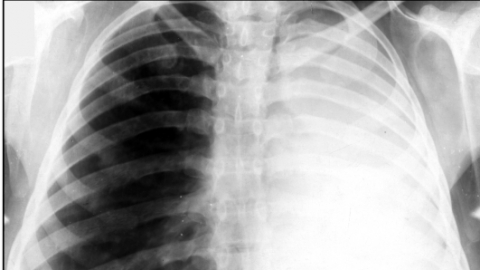

Ателектаз легких у новорожденных

У здоровых новорожденных — преимущественно у недоношенных — ателектаз легкого (частичный) может отмечаться в первые несколько суток жизни. Как правило, такие ателектазы исчезают без какого бы то ни было вмешательства и потому считаются «физиологическими».

Причины возникновения ателектаза у новорожденных разные: это и вдыхание некоторого количества околоплодных вод, и недостаточное содержание так называемого сурфактанта (особого вещества, которое не дает спадаться легочной ткани), и неполное расправление сети легочных сосудов, а также слабый крик при рождении и ослабленное дыхание, в результате чего легкое новорожденного не разворачивается полностью.

Кроме того, ателектазы могут развиться при асфиксии, при пневмониях, при давлении на бронхи увеличенных внутригрудных лимфатических узлов и т.д.

В зависимости от величины и локализации пораженного участка легкого развиваются клинические проявления. Довольно часто за клинической картиной основного заболевания не видно проявлений ателектаза. Кожные покровы у новорожденного могут быть бледны или синюшны; у ребенка — явная одышка. Врач, прослушивающий легкие с помощью фонендоскопа, не слышит дыхания в том месте, которое поражено, или слышит ослабленное дыхание. Перкуторный звук над участком ателектаза укорочен.

Помимо опроса и объективного осмотра, включающего перкуссию и аускультацию грудной клетки, проводят рентгенологическое исследование в двух положениях тела (в 2-х проекциях). Это основной метод обнаружения ателектазов легких.

На рентгеновских снимках выявляют следующие признаки, указывающие на спадение легочной ткани:

Однородное затемнение в области поражения. Размеры тени зависят от вида ателектаза: при долевом выявляется обширное затемнение, при сегментарном — в виде клина или треугольника, расположенного вершиной к корню легкого, дольковые ателектазы множественные и похожи на очаговую пневмонию. Дистензионный ателектаз расположен низко, около диафрагмы, имеет небольшие размеры и вид поперечных полос или темных дисков. Смещение органов: при компрессионном ателектазе смещение наблюдается в здоровую сторону, так как на стороне поражения давление больше, при обтурационном, наоборот – смещение будет в сторону ателектаза, так как на стороне поражения нарастает притягивающее отрицательное давление. Подъем купола диафрагмы – это видно по расположению печени.